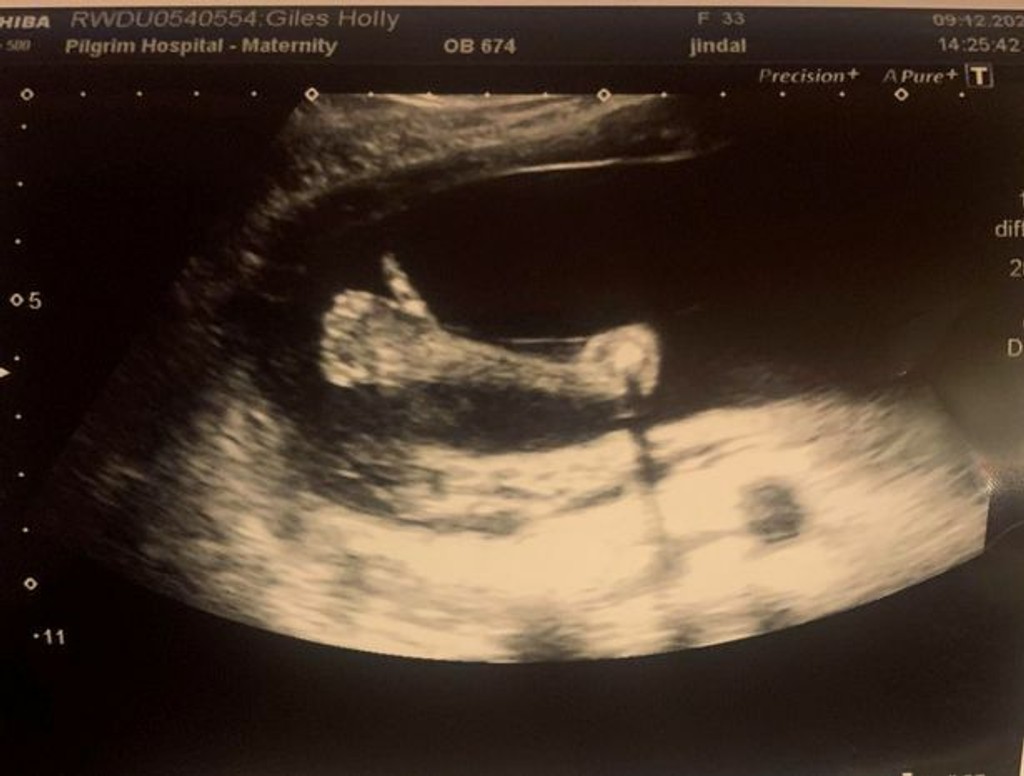

Uvidieť počas sonografického vyšetrenia svoje nenarodené dieťa je pre väčšinou budúcich mamičiek najkrajším zážitkom. Holly Gilesovú (33) z Horncastle v anglickom grófstve Lincolnshire záber na monitore doslova vyrazil dych, píše Mirror.

Tridsaťtriročná učiteľská asistentka v dvadsiatom týždni tehotenstva totiž na monitore uvidela, ako jej dieťatko ukázalo palec hore, akoby naznačovalo, že je všetko v poriadku.

Ako prvá zbadala nezvyčajný odkaz pôrodná asistentka. „Povedala, že je to naozaj zriedkavé a nikdy predtým nič také nevidela,“ uviedla Gilesová. S budúcou mamičkou bola na vyšetrení aj kamarátka, ktorá stihla prekvapujúci moment odfotiť.

Holly tento moment dojal k slzám, pretože ešte donedávna si nebola istá, či bude môcť otehotnieť. Ako šestnásťročná tínedžerka navyše sama stratila matku, ktorá jej teraz chýba ešte viac ako inokedy. „Mám pocit, akoby to malé bolo darom od mojej mamy,“ povedala.

Pohlavie bábätka budúca mamička ešte nepozná. Svojho malého pokladu sa podľa vlastných slov už nevie dočkať.